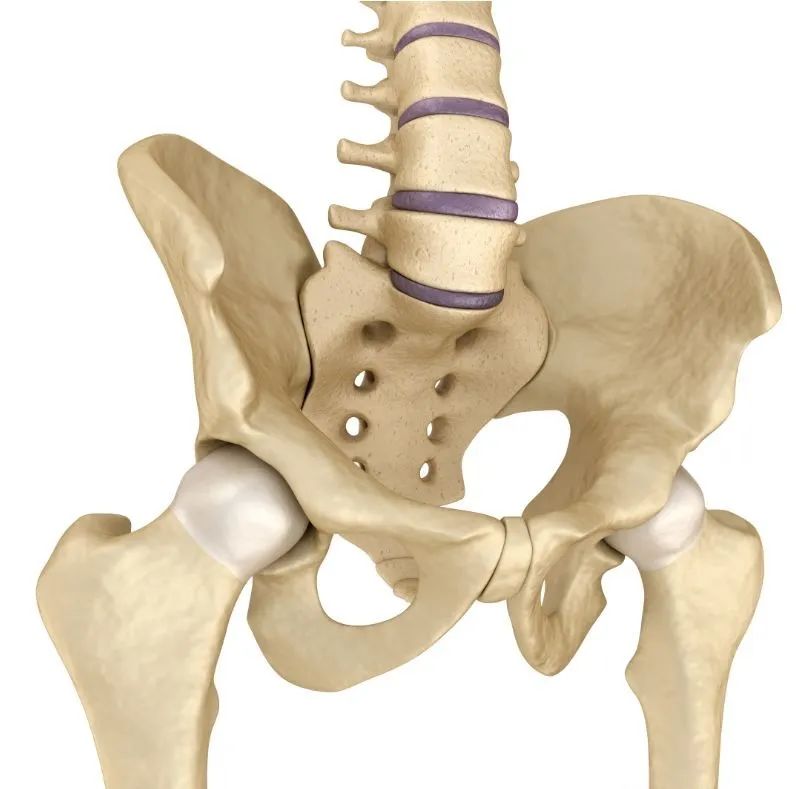

脊柱是人体的大梁,骨盆是其坚实的基座,骨盆旋移可引起腰骶痛、长短腿、足外翻及盆腔脏器功能异常,如痛经、阴道残端脱垂及漏尿等,常规的对症治疗,往往效果不佳,对骨盆旋移综合征的病因、发病机制进行了解,才能从根本上解除病痛。